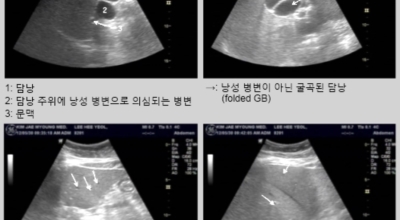

쓸개 초음파 검사는 담낭과 담도를 확인하는 것입니다. 담낭용종, 담낭결석, 담석증, 담낭염, 담도 질환 등을 확인할 수 있습니다.

오른쪽 갈비뼈 아래와 옆구리 통증으로 인해 병원을 방문하였다가 복부 초음파를 통하여 ‘급성 담낭염’ 진단을 받는 경우가 있답니다. 담낭 질환도 1개입니다. 급성 담낭염의 경우 CT, MRI와 같은 검사보다 복부 초음파로 검사하는 것이 정확도가 상대적으로 높는 것으로 알려져 있어요. 담낭은 간의 아래쪽 경계면에 위치하고 있고 급성 담낭염이란 담낭 내 담즙이 비워지지 않을 경우 발생하는 질환으로 담낭 내부에 있는 돌인 ‘담낭결석’과 90% 이상 관련이 되어 있답니다.

이 결석이 담낭 내 담즙이 지나가는 통로를 막고 있으므로 담즙이 소장으로 흘러가지 못하게 되고 이에 따라 감염이 발생해 증상이 나타날 수 있답니다. 담낭염은 복부 초음파로 알 수 있는 것이므로 증상이 나타나면 검사를 받아볼 수 있답니다. 복부 위에 통증이 간헐적으로 발생하고 시간이 지날수록 열과 오한이 동반된다면 의심해 볼 필요가 있어요. 복부 초음파로 통해 ‘담낭결석’을 확인할 수 있을 뿐만 아니라담낭의 크기와 담낭 벽의 두께까지 알 수 있기 때문에 정확한 상태를 관찰할 수 있어요.